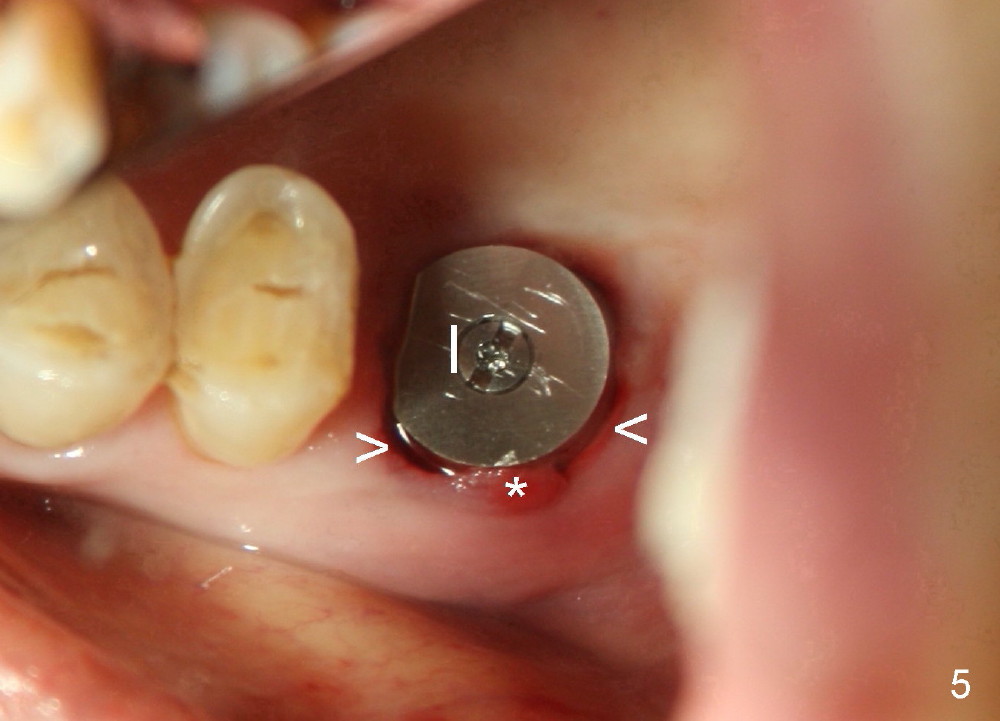

The tooth #14 of a 79-year-old lady is also non salvageable (Fig.4), but this patient chooses immediate implant (Fig.5, 8x14 mm, no bone graft). The socket heals uneventfully (Fig.6, 2 weeks postop). The implant has been in function for 11 months.